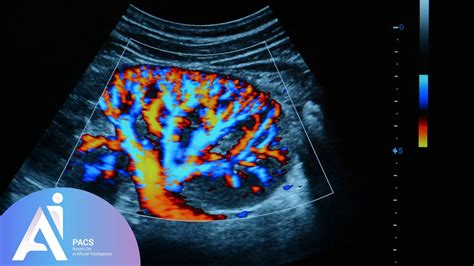

During the procedure, the sonographer or radiologist evaluates specific blood vessels to determine how well oxygen and nutrients are being delivered to the fetus. The primary areas of interest include:

Umbilical Artery Checks blood flow resistance between the placenta and the fetus.